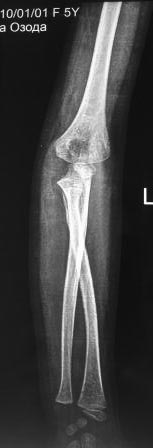

Обратилась девочка 2010г.р., 8 месяцев назад в результате падения на

руку получила травму, гипсовая повязка , которую сняли через неделя и

дальше не лечилась, со слов матери постепенно нарастает деформация.

Объективно отмечается волярное выбухание головки лучевой кости, и

гиперэкстензия в локтевом суставе, функция почти не нарушена, супинация

и пронация сохранены. Какой-то чувство, что возможно была разгибательный

переломо-вывих Монтеджа. Фото руки и Р-снимки представляются.